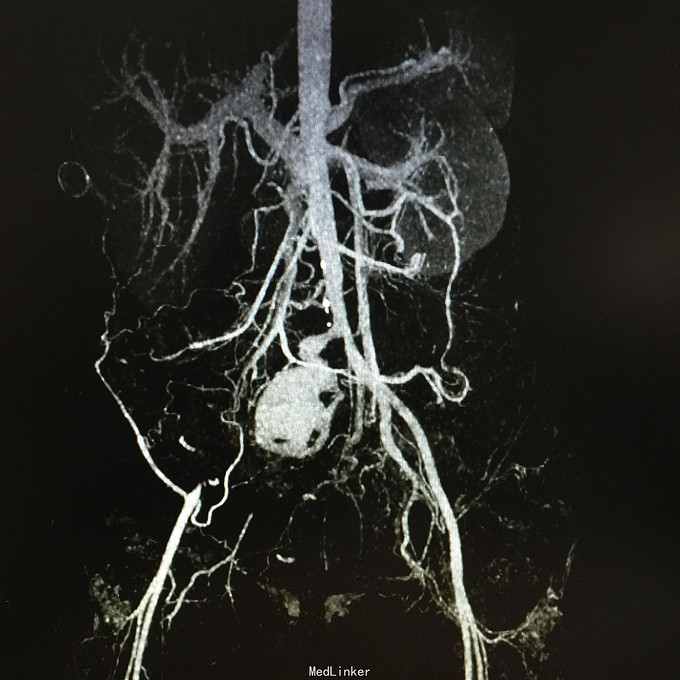

查体无特殊。 辅助检查:中下腹CT平扫+增强+CTU+CTA示:1.右输尿管中上段病变,考虑恶性病变,周围多发淋巴结转移,髂总动脉及髂外动脉起始部、髂内动脉中上段受侵闭塞,右侧腰大肌可疑受侵;建议输尿管镜检查;右肾重度积水,右肾功能明显受损。2.CTA示:右肾动脉纤细,肝右动脉起源于肠系膜上动脉。3.子宫体密度不均匀,建议MRI检查。中下腹MRI平扫+增强+MRU检查结果类似。

患者术后2月出现反复臀部疼痛,左侧为主,疼痛跑迷宫为隐痛,于翻身及活动时加重,卧床休息可稍缓解,多于下午出现,伴有发热,最高达39℃,在当地医院予“氟康唑”及止痛治疗后稍有缓解,但仍反复发热。后疼痛加剧,并出现双下肢疼痛,以大腿外侧为主,无间歇性跛行,无小腿及双足麻木疼痛不适,行对症治疗后效果不佳,于2015-10-9再次返院,予消炎止痛、营养支持及营养神经等治疗。查CT及MRI均提示骶髂关节炎症及腹膜后巨大病变,右侧髂总动脉及髂内、外动脉上段、右侧腰大肌受累。2015-10-15 14:00患者出现右下肢剧烈疼痛、右下肢乏力和麻木,随后出现2次血便,每次量约100ml,暗红色,无腹胀、腹痛等不适,查血提示白细胞 28.17*10E9/L,中性粒绝对值 25.33*10E9/L,血红蛋白56g/L,予止血、输血、抗真菌、止痛等治疗。19:00再次出现右下肢剧烈疼痛伴右下腹痛,查体:BP 80-90/50-60mmHg,P 100-106次/分,R 23次/分,SpO2 100%。右下腹轻压痛,反跳痛阴性,右下肢蹲背伸及踝背伸肌力II-III级,立即行全腹CT检查,示右髂总动脉假性动脉瘤破裂,予加强输注浓缩红细胞及补液支持治疗。清介入科会诊,考虑脓肿和感染为介入血管腔内支架置入治疗的禁忌症,建议予血管外科行开放手术,予患者及家属沟通,并转外院血管外科进一步治疗。